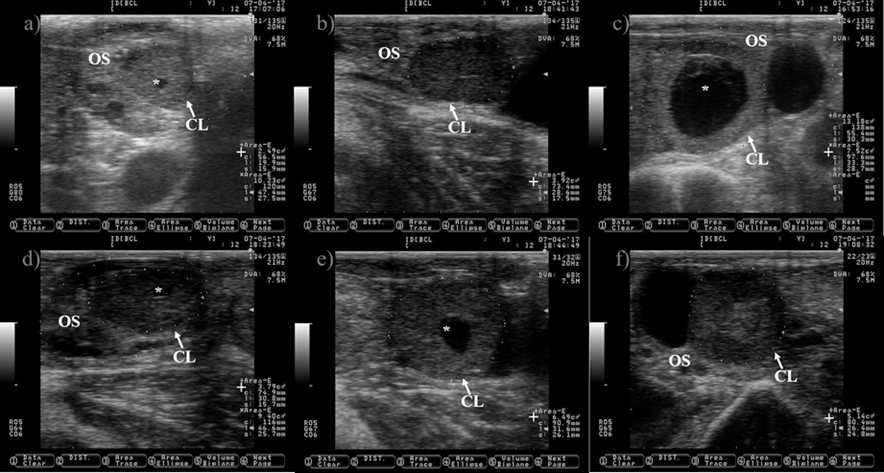

Ultrasound allows to visualize only the selection and dominance phase of the follicular wave, but not the recruitment phase because it takes place at very early stage of follicular development. The preovulatory follicle at day zero and the subsequent corpus luteum were located in the left ovary, but only pictures of the right ovary are shown because is where the follicle wave emerged. a) a small antral follicle is encircled with a dotted line at day zero (the anechogenic characteristics of the follicular fluid makes the follicle appears as dark circle), gray arrows are indicating the presence of other two antral follicles. b) the follicle wave has emerged, the four follicles are encircled with dotted lines at day one, three of them were previously observed at day zero (gray arrows). c) the gray arrows are pointing to the three follicles observed since day one, the increase in its size is easily observed at day two. The growth of the three follicles (dotted lines) observed since day zero is depicted in Pictures c) and d) (day three and four). e) the dominant follicle of the follicular wave is selected (selection of the dominant follicle occurs when the largest follicle reaches approximately 8.5 mm in diameter11), this marks the end of the selection and the commencement of the dominance phase. The growth of the dominant follicle (dashed arrows) and the atresia of the subordinate follicles (white lines) are depicted in Pictures g) to i). OS: ovary stroma. White arrow: day of the estrous cycle. Pictures were taken using a 7.5 MHz probe.

Figure 1 Pictures depicting follicle wave growth in dairy cattle from estrus (day 0) to day 11 of the estrous cycle

Pictures were taken at approximately every 24 h from day before to 7 d after ovulation. a) preovulatory follicle (PF). b) early CL after ovulation of the PF, notice the presences of luteal cavity (*), the CL and the ovary stroma (OS) are almost isoechogenic until 2 d after ovulation (b-d), but the CL becomes darker (hypoechogenic) than the OS as it ages (c-i). e) the CL is well differentiated from the OS at 3 d after ovulation. f-i) pictures depict a growing CL, the luteal cavity is clearly identified at this stage (4-7 d after ovulation). i) the CL has almost triple its area (+) since ovulation day (b). Pictures were taken using a 7.5 MHz probe.

Figure 4 Growth of the corpus luteum (CL) after ovulation in Holstein dairy cattle